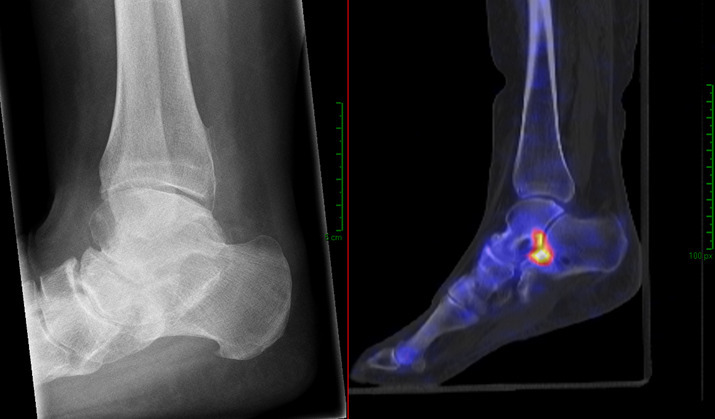

Abstract Image